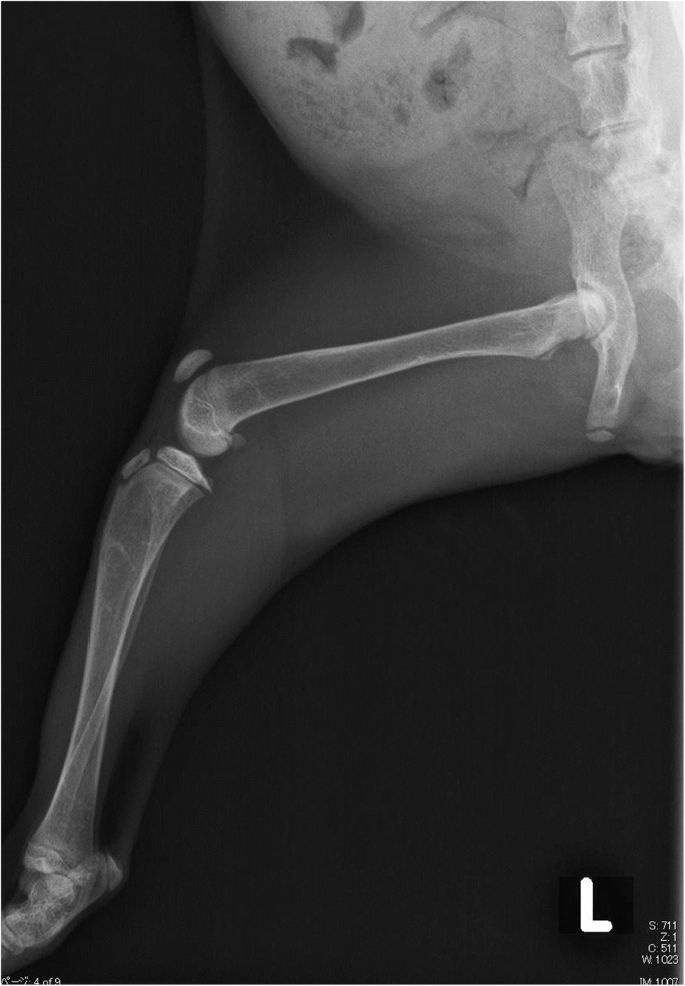

On initial examination, the cat was lethargic and reluctant to move. Her appetite was good, but defecation appeared to be painful. Her family history, including whether the parents and littermates were alive, was unknown. Serum biochemistry revealed that both the total and ionized calcium levels were low (total calcium 1.55 mmol/L; reference range 2.05–3.02 mmol/L, ionized calcium 0.74 mmol/L; reference range 1.20–1.35 mmol/L). Radiographs showed skeletal demineralization and the presence of abnormally wide growth plates on the long bones (Fig. 2). The differential diagnosis for hypocalcemia with skeletal abnormalities includes primary hypoparathyroidism, nutritional secondary hyperparathyroidism, renal secondary hyperparathyroidism, intestinal malabsorption, and VDDR. However, the cat had previously eaten a well-balanced commercial kitten food (Science Diet kitten, Hill’s Colgate Japan) before becoming obviously ill, so nutritional deficiency seemed highly unlikely. The levels of parathyroid hormone (Immulyze intact PTH III, Simens) and 1,25-dihydroxycholecalciferol (1,25(OH)2D RIA Kit FR, Immunodiagnostic Systems) were determined as elements of the differential diagnosis of hypocalcemia. The parathyroid hormone level was high (99.7 pg/ml; reference range 8.0–25.0 pg/ml), but 1,25-dihydroxycholecalciferol (23.1 pg/ml) was low compared with the levels of healthy cats (Table 2). The urinalysis revealed a specific gravity of 1.032 and traces of protein. No bacterial growth was detected in the urine culture. Consequently, VDDR was suspected to be the cause of hypocalcemia and skeletal abnormalities in this cat.

Starting on day 2, the cat received alfacalcidol (Onealfa Tablets) by CRI of 8.5% calcium gluconate. However, she did not respond well to treatment with the standard dose (0.01–0.03 μg/kg, PO, SID) of alfacalcidol so the CRI of 8.5% calcium gluconate was stopped. The final dose of alfacalcidol was very large, and 1 μg/kg, PO, TID was required to maintain the cat’s general condition in the absence of CRI of 8.5% calcium gluconate (Table 3). On day 16, the cat was discharged from hospital. Radiographs were taken again 2.5 months after the initial treatment was started. The cat’s bone structure was still abnormal, but showed marked improvement (Fig. 3).